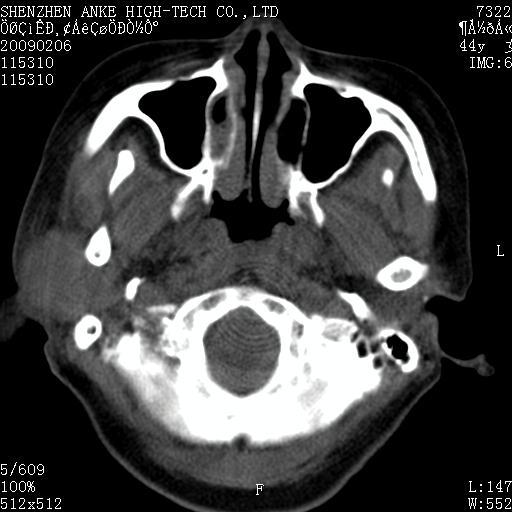

标题: CT17977:女,44岁,右侧颌部包块1年,右侧面瘫2月。 [打印本页]

患者:女,44岁,右侧颌部包块1年,右侧面瘫2月。

考虑右侧腮腺混合瘤可能性大

考虑右侧腮腺混合瘤;不排除腮腺癌。

右侧腮腺肿瘤,良恶性难定。